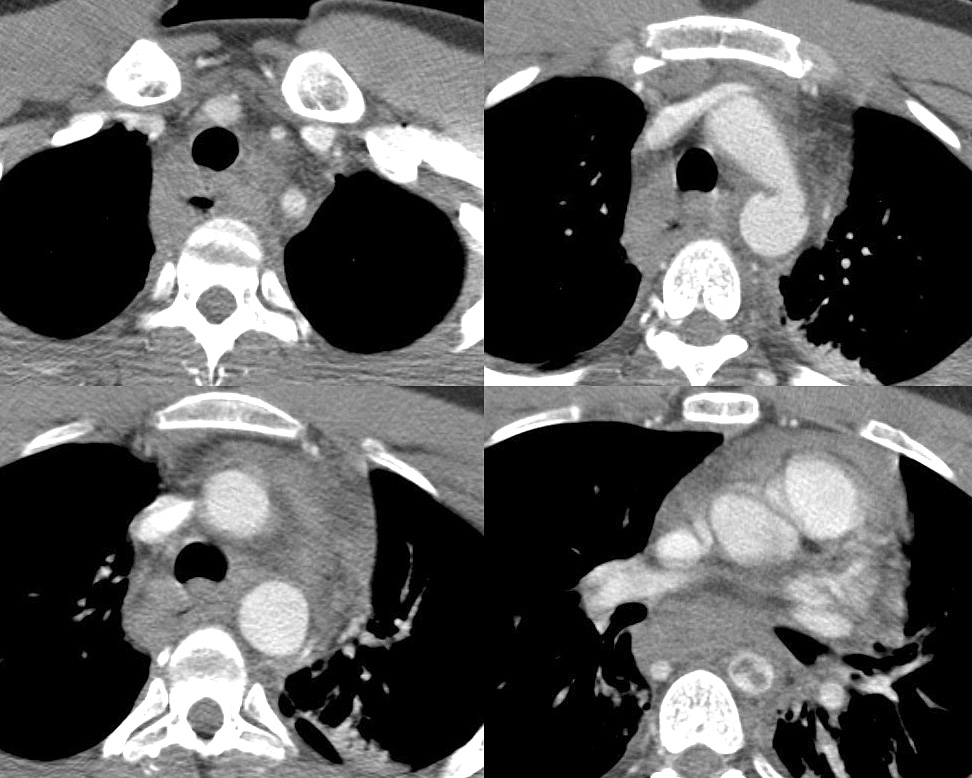

Gallery Blunt Chest Trauma Tr Aortic Injury Case 6c

Case 6c